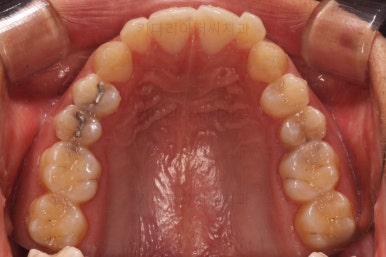

초진 시 입안의 모습입니다.

앞니가 약간 삐뚠 것 말고는 큰 문제는 없어보이네요.

장치를 부착했습니다.

이번 부산연제구교정 환자분이 선택한 장치는 엠파워 클리어라고 하는 자가결찰 세라믹 장치입니다.